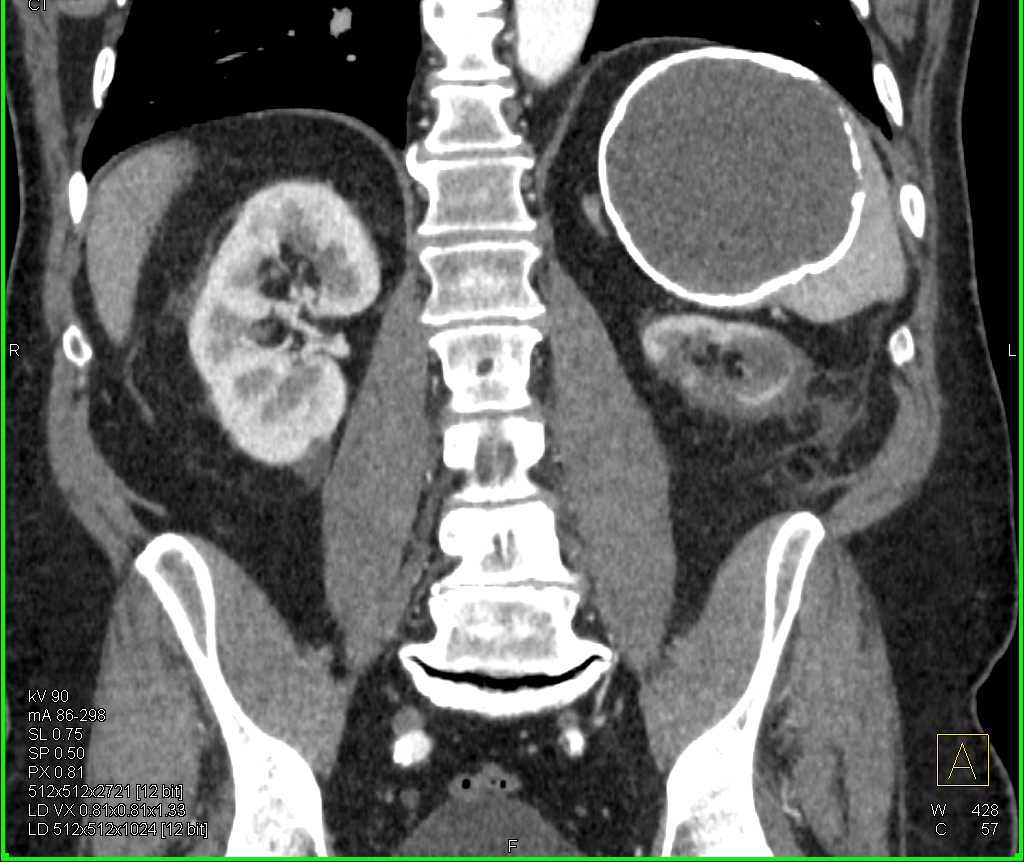

Gaucher's Spleen